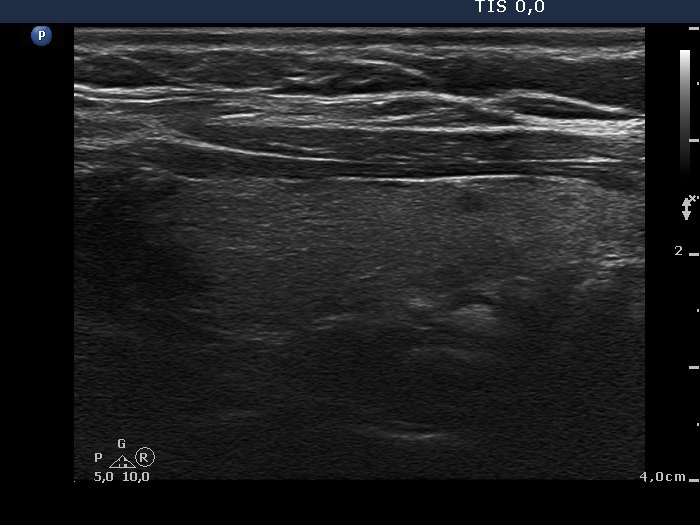

100 consecutive cases of papillary cancer - case 003 (ultrasonographic picture 5)

Left lobe, longitudinal scan.